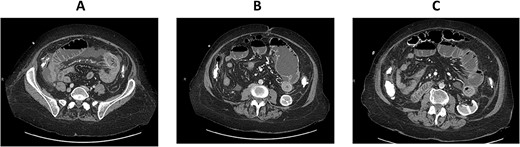

CT enterography: axial views demonstrating dilatation of the bowel loops in the left lower quadrant associated with bowel thickening and collapsed small bowel loops distally.

The patient is a 71-year-old white female with a past medical history of PSC who underwent orthotopic deceased donor liver transplant in 2006 with a Roux-en-Y hepaticojejunostomy biliary anastomosis. Cholecystectomy was performed to the donor liver. Her course has been complicated over the years by recurrent cholangitis requiring a permanent percutaneous biliary drainage tube. The patient had a liver biopsy in 2011 which showed recurrent PSC, but the patient refused any further liver transplants. Her daily immunosuppressive regimen consisted of cyclosporine 25 mg. Thirteen years after the deceased donor liver transplant, the patient presented to our emergency department with abdominal pain for a week which was associated with abdominal distention and nausea. Her liver function tests and complete blood count were normal on admission. Computed tomography (CT) scan of her abdomen and pelvis with intravenous contrast demonstrated focal dilatation of proximal jejunal bowel loop at the site of anastomosis with air-fluid/debris level (Supplementary Figure 1). She was admitted to the hospital and was initially managed conservatively with nasogastric tube suction, bowel rest and intravenous fluid hydration. A small-bowel follow-through study was obtained which revealed contrast within the colon with no radiographic evidence of bowel obstruction. The patient’s clinical condition improved on her second day after admission and a trial of diet was performed, but the patient had worsening symptoms and subsequently developed peritonitis on her fourth hospital day. CT enterography was obtained which revealed dilatation of the proximal small bowel loops proximal to the small bowel anastomosis in the left mid-abdomen with mild wall thickening of the small bowel in the left lower quadrant without definitive obstructing cause or evidence of pneumatosis (Figs 1A–C and 2A,B). The patient was taken emergently to the operating room for an exploratory laparotomy. The jejunojejunostomy was intact and dilated with dilated proximal Roux limb. Approximately, 50 cm distal to the jejunojejunostomy in the common limb, a firm, round mass was palpated in a segment of bowel which was very edematous, friable, inflamed, with a focus of necrosis without obvious perforation. The remainder of the small bowel was normal. Given the state of the small bowel with the focus of necrosis, the decision was made to perform a small bowel resection with a hand-sewn anastomosis. The resected small bowel was opened off the field, and an impacted bezoar was found with small circular yellowish objects thought to possibly be gallstones mixed with other fibrous content. The resected small bowel pathology showed focal mucosal ulceration, transmural hemorrhage and acute serositis. The patient had an uneventful post-operative course and was discharged home 7 days after surgery. She was seen in clinic for a follow-up appointment a month after the surgery and was found to be doing great, tolerating her diet and having regular bowel function.